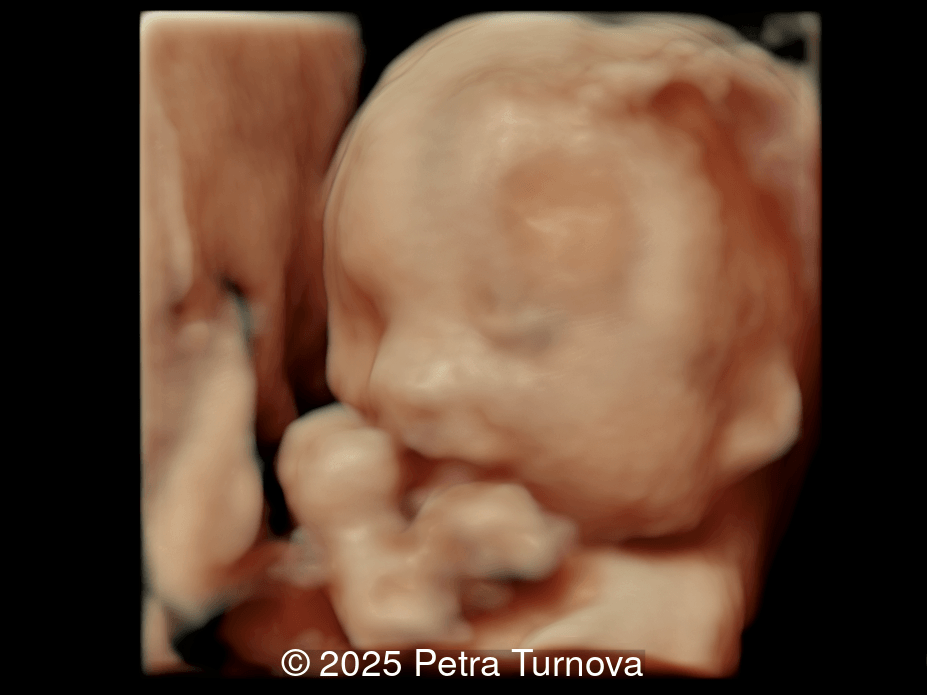

A woman with no significant medical history presented to our center at 20 weeks and 5 days for fetal anatomic survey. The following findings were observed:

Image 1

Our imaging revealed malformations in all four limbs with elbow, wrist, and knee joints fixed in extension, as well as foot and ankle malformations. Profile abnormalities were observed with prefrontal edema, flat profile and retro-micrognathia. Ultrasound demonstrated minimal stomach filling related to a lack of swallowing ability and hypoplastic lungs due to poor diaphragmatic movement. Nuchal edema was present.